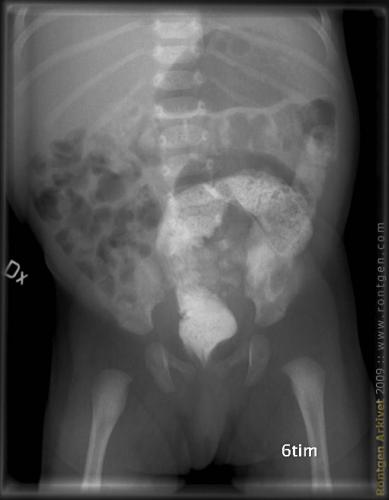

Anografi

Anografi på 2 månaders baby med kontrast i ändtarmen för funktion av tömning.

Frontal bild.